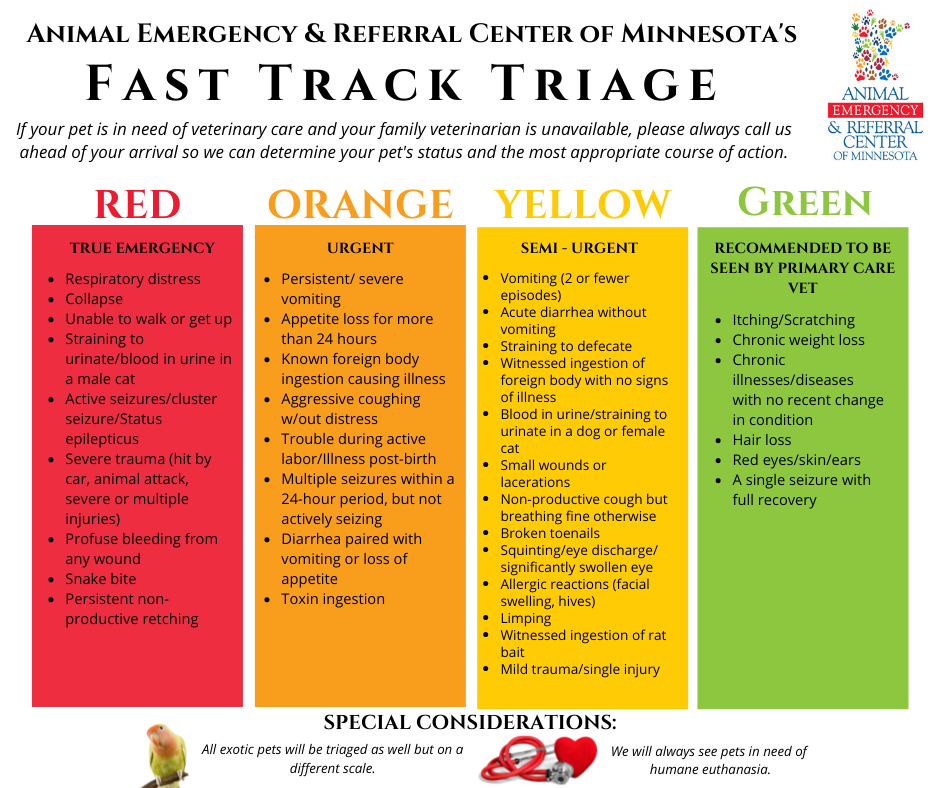

Digital Radiographs (X-Rays)

Digital radiographs, better known as x-rays, are typically used to image bones such as a broken bone or a stress fracture. They can also be used to diagnose conditions like arthritis or kidney stones. Our Dentistry & Oral Surgery Service also frequently uses dental x-rays to fully evaluate a pet’s mouth.

X-rays are widely available in most veterinary clinics and can be performed 24/7 with rapid evaluation – especially important for emergency veterinarians. However, since x-ray images are literal shadows of the internal organs, your veterinarian may also need ultrasound, CT, or MRI to provide a more detailed look at internal structures.

X-ray image of a dog’s abdomen. There is cloth-like foreign material in the stomach causing obstruction, as well as a string-like foreign material in the intestines causing bunching and obstruction. This is a surgical emergency to prevent severe injury to the intestines and abdomen.